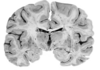

What type of posturing is this person displaying? [1]

1 - superior temporal gyrus; 2 - inferior frontal gyrus; 3 - insular cortex; 4 - temporal stem; **5 - internal capsule;** **6 - thalamus;** **7 - lentiform nucleus** (the internal and external globus pallidus and the putamen) 8 - frontal horn; 9 - superior circular sulcus; 10 - inferior circular sulcus.